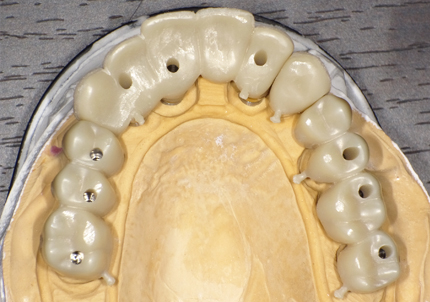

21.ジルコニアブリッジ試適(2020年12月)

22.最終補綴物完成・装着口腔内写真(2021年1月)